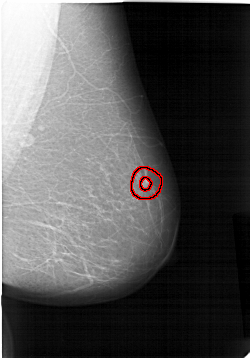

FILE: A_1159_1.RIGHT_MLO.OVERLAY

TOTAL_ABNORMALITIES 1

ABNORMALITY 1

LESION_TYPE MASS SHAPE IRREGULAR MARGINS SPICULATED

ASSESSMENT 5

SUBTLETY 5

PATHOLOGY MALIGNANT

TOTAL_OUTLINES 2

RIGHT_MLO LINES 6436 PIXELS_PER_LINE 4486 BITS_PER_PIXEL 12 RESOLUTION 43.5 OVERLAY